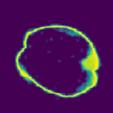

Despite the state-of-the-art performance for medical image segmentation, deep convolutional neural networks (CNNs) have rarely provided uncertainty estimations regarding their segmentation outputs, e.g., model (epistemic) and image-based (aleatoric) uncertainties. In this work, we analyze these different types of uncertainties for CNN-based 2D and 3D medical image segmentation tasks. We additionally propose a test-time augmentation-based aleatoric uncertainty to analyze the effect of different transformations of the input image on the segmentation output. Test-time augmentation has been previously used to improve segmentation accuracy, yet not been formulated in a consistent mathematical framework. Hence, we also propose a theoretical formulation of test-time augmentation, where a distribution of the prediction is estimated by Monte Carlo simulation with prior distributions of parameters in an image acquisition model that involves image transformations and noise. We compare and combine our proposed aleatoric uncertainty with model uncertainty. Experiments with segmentation of fetal brains and brain tumors from 2D and 3D Magnetic Resonance Images (MRI) showed that 1) the test-time augmentation-based aleatoric uncertainty provides a better uncertainty estimation than calculating the test-time dropout-based model uncertainty alone and helps to reduce overconfident incorrect predictions, and 2) our test-time augmentation outperforms a single-prediction baseline and dropout-based multiple predictions.